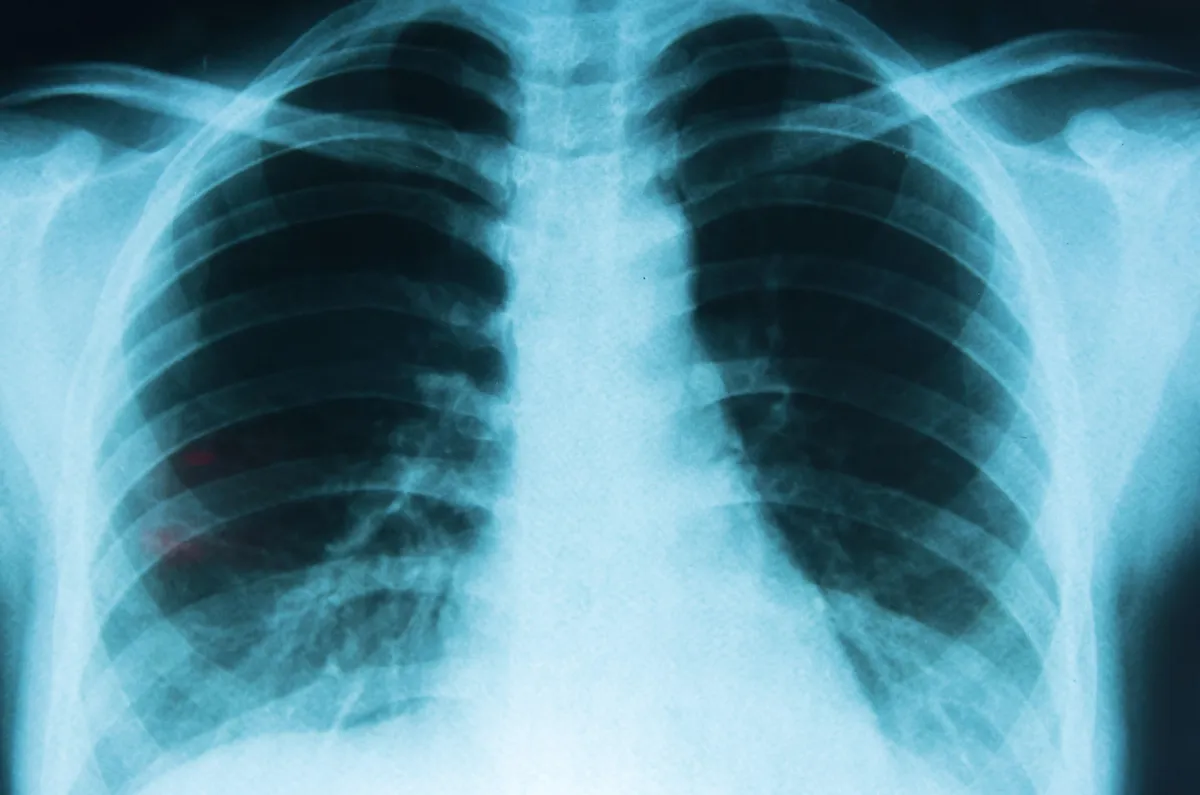

Argentina pone a disposición un nuevo tratamiento contra el cáncer de pulmón

Llega al país un nuevo anticuerpo monoclonal que ofrece nuevas perspectivas para pacientes con un tipo específico de esta enfermedad.

Argentina da la bienvenida a un nuevo tratamiento para un tipo particular de cáncer de pulmón. Se trata de amivantamab, un anticuerpo monoclonal que demostró eficacia para personas con una mutación específica dentro del subtipo de cáncer de pulmón denominado "de células no pequeñas" (CPCNP) en estadio avanzado o metastásico.